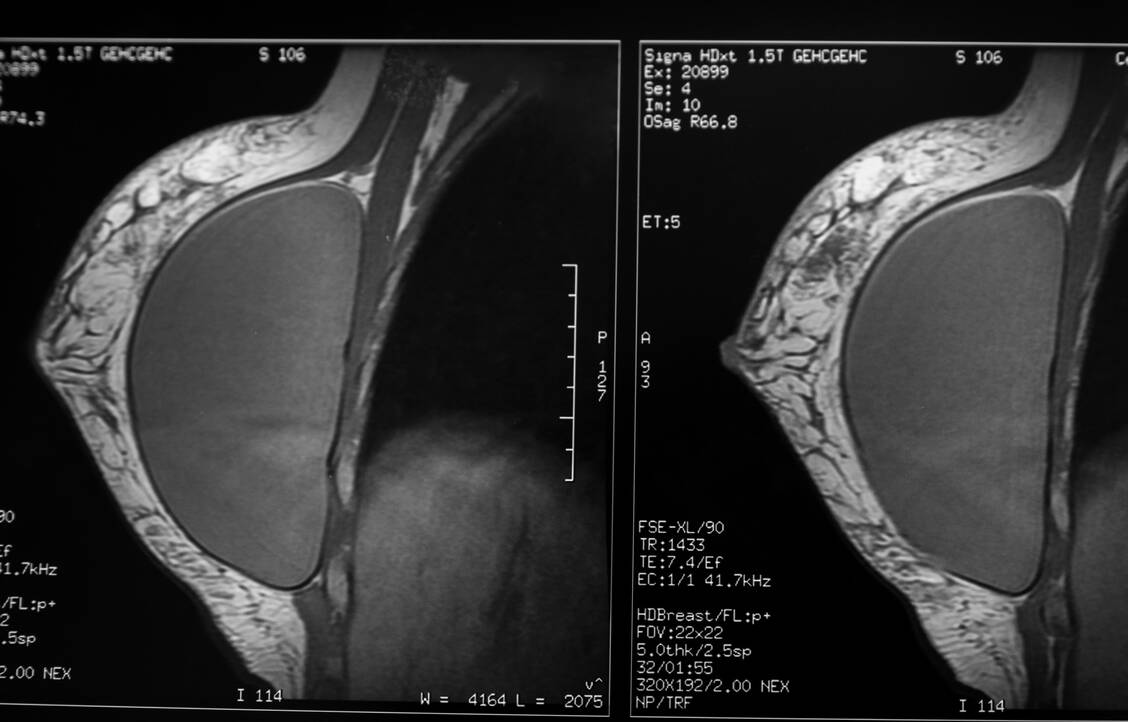

Bei einer Mammographie werden Röntgenaufnahmen von den Brüsten angefertigt. Dazu werden diese zwischen zwei Plexiglasplatten gelegt und zusammengedrückt. Doch wie funktioniert das bei Frauen, die sich einer kosmetischen Brustvergrößerung unterzogen haben und Implantate tragen? Können diese dabei beschädigt werden? Und lässt sich auf den Röntgenbildern überhaupt etwas erkennen?

Betroffene Frauen sollten jedoch wissen, dass die Untersuchung selbst unangenehm oder schmerzhaft sein könne, vor allem, wenn etwa das Gewebe um die Implantate stark vernarbt ist oder sich eine Kapselfibrose gebildet hat. Zudem können die Implantate eine Beurteilung der Röntgenaufnahmen erschweren. Dann werden dem DKFZ zufolge unter Umständen zusätzliche Untersuchungen wie Ultraschall oder eine Magnetresonanztomographie (MRT) notwendig.